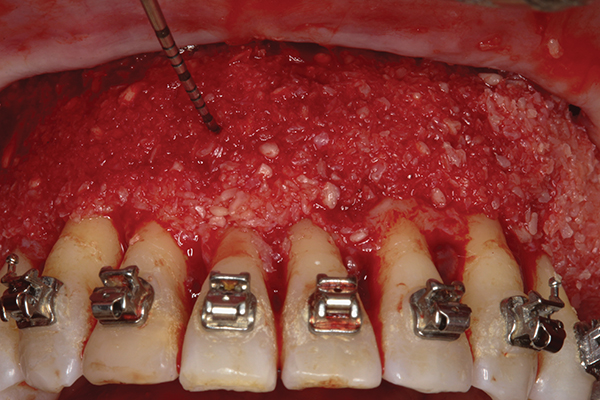

Fig 2. Full-thickness flap reflection. Note

dehiscence and fenestrations throughout. Orthodontic walls are limited to nonexistent.

Fig 3. Corticotomy cuts performed.

Figure 3